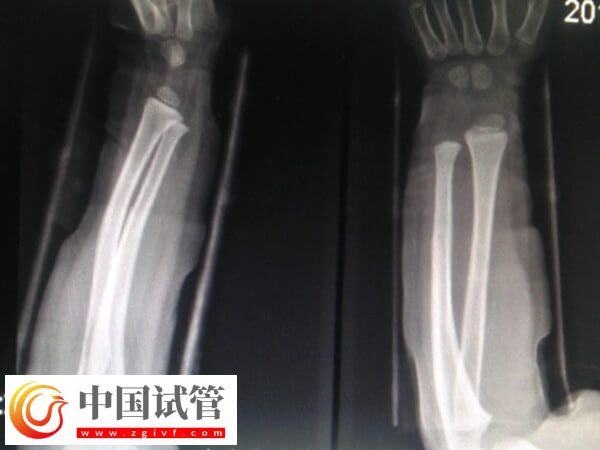

患者骨折愈合一年之后一般是可以做试管婴儿的,这时骨折部位已经基本恢复稳定,身体也基本恢复到正常状态,所以不会对试管婴儿的整个流程产生直接的不良影响。不过为了确保妊娠的安全性,建议患者一定要注意观察身体状态,以及骨折位置,若是有任何异常,则建议及时就医,以提高试管妊娠成功率。

骨折过的人,多数能够恢复到原来正常水平一样。因为大多数的骨折都可以得到及时的正确的复位,都能恢复到原来正常水平一样。所以骨折愈合一年后是可以做试管婴儿的,但为了确保骨折位置和妊娠的安全性,建议患者还要注意以下几点事项。